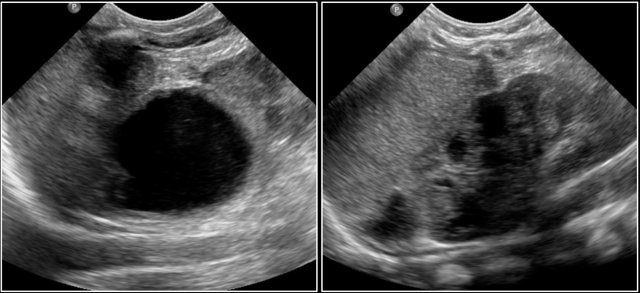

The US- image shows a cystic lesion in the lower abdomen in a 3-year-old girl with colicky abdominal pain.

At operation a torsion of the right adnex was seen.

On pathology a teratoma was demonstrated.

Two-year-old girl with a sacral mass. On ultrasound a cystic lesion anterior to the sacrum is seen, compatible with a class 4 sacrococcygeal teratoma. It was completely resected.

The intraspinal extension was visible on ultrasound, but MRI provides a better overview and a document for future comparison.

A parasagittal MRI shows a presacral cystic mass.

Newborn girl with a sacrococcygeal teratoma with external and internal solid and cystic parts, and a large intraspinal extension.